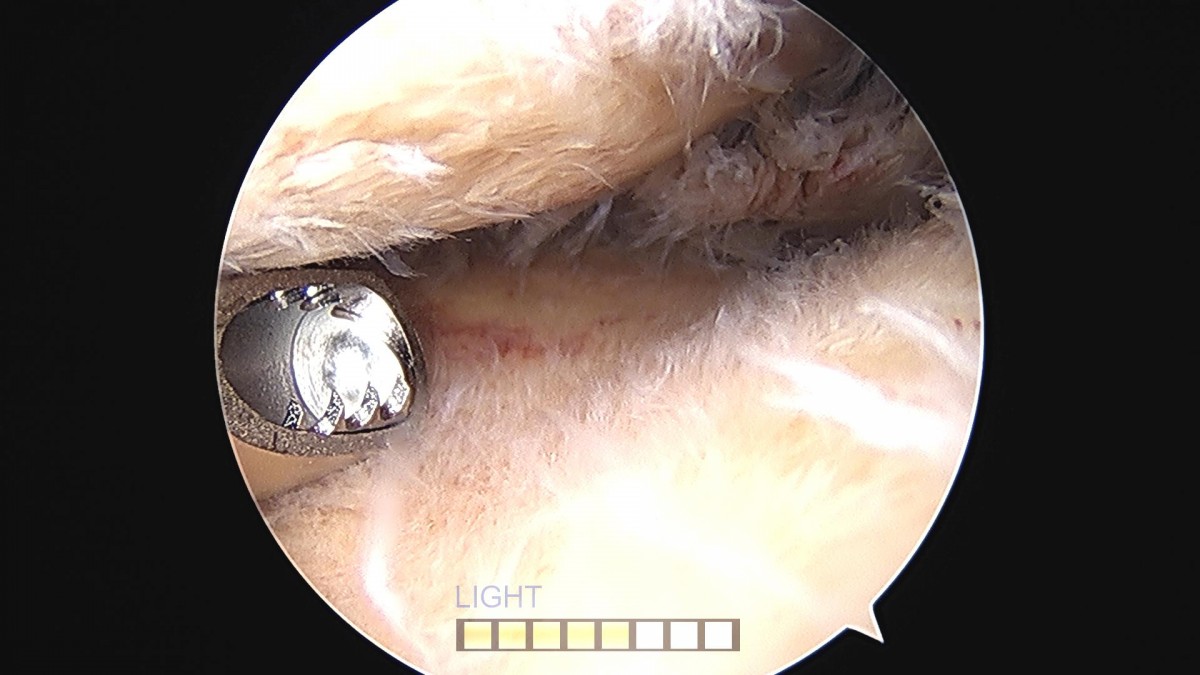

배우한원장님 무릎 내측 반월상 연골판 절제술 및 무릎 골절 수술 안중O 환자

작성자 최고관리자 댓글 0건 조회 2,203회 작성일 22-12-08 17:26